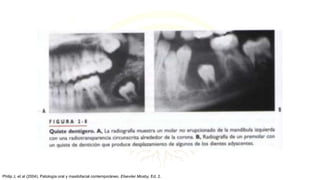

QUISTE DENTÍGERO

• Quiste odontogeno que rodea la corona de un diente

impactado; se debe a acumulación de liquido entre el

epitelio reducido del esmalte y la superficie del esmalte,

produciéndose un quiste en cuya luz esta situada la corona

mientras la raíz (o raíces) permanecen por fuera.

• Comúnmente asociados con terceros molares mandibulares

o del maxilar superior, o con caminos no erupcionados del

maxilar superior.

RADIOLOGÍA:

• Se diagnostican con mayor frecuencia por su aspecto

radiográfico.

• Radiotransparencias bien circunscritas que rodean la corona

de un diente.

• En la mandíbula, este quiste puede desplazar al diente

asociado en dirección caudal o craneal hacia la rama

ascendente de la mandíbula.

• En el maxilar superior suele desplazar al diente asociado

hacia arriba y hacia atrás.

Philip J, et al (2004). Patología oral y maxilofacial contemporáneo. Elseviier Mosby, Ed. 2.